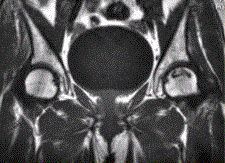

问题 患者男,47岁,左髋部疼痛及压痛6个月,“4”字试验阳性。左髋关节内、外旋活动受限。检查提示:左髋关节活动轻度受限,大腿上部轻压痛。血常规检查正常。髋关节CT及MRI如下图。 对本病例,你首先考虑的诊断是

选项 A.骨髓炎 B.左股骨头缺血性坏死 C.退行性关节病 D.关节结核 E.骨岛 F.左髋关节腔积液

答案 BF